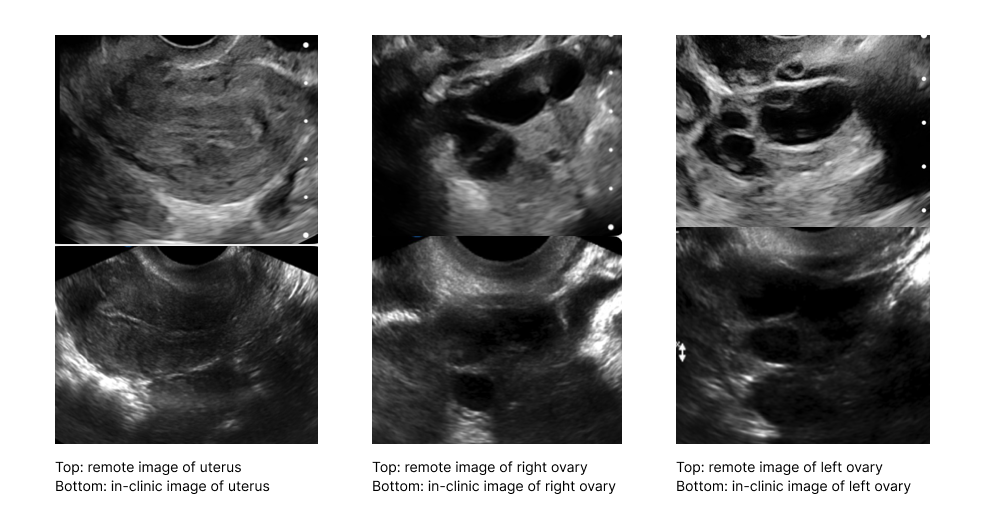

Recent advances in remote ultrasound technology now allow us to provide patients with the same high-quality imaging remotely as one would receive in a traditional clinic setting.

At Sama Fertility, our pilot study has demonstrated that remote self-administered transvaginal ultrasound devices produce clinically reliable images, an essential part of successful fertility treatments.

The Sama Remote Ultrasound Study compared oocyte retrieval outcomes between patients using a remote care model and those receiving in-clinic treatment. The results showed no significant difference in egg retrieval success between the two groups, highlighting the effectiveness of remotely guided ultrasounds.

Further validating this approach, independent studies by Chung et al. and Resetkova et al. demonstrated that remote transvaginal scans are comparably reliable to those performed in clinics.